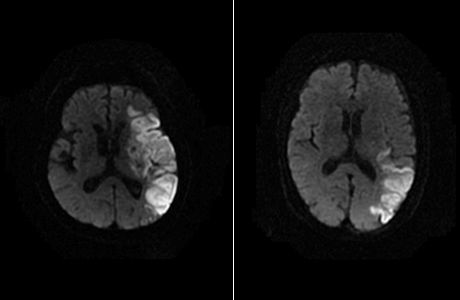

• 뇌 핵자기 공명술 및 혈관촬영(MRI/MRA)

MRI/MRA는 CT에서 찾기 힘들 정도의 작은 병변이나 뇌간 부위의 병소를 정확히 찾을 수 있는 장점이 있습니다. 혈관촬영(MRA)은 침습적 방법을 하지 않고도 뇌혈관 상태를 파악할 수 있습니다.